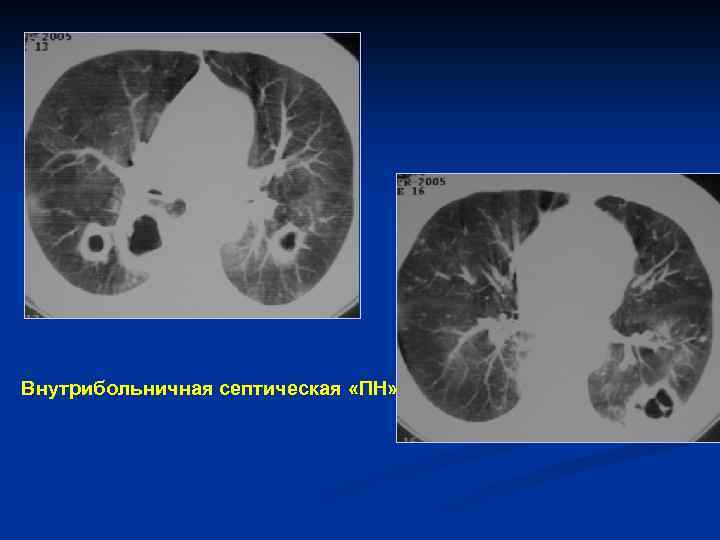

3 Пациентка 48 лет, с аспириновой астмой , длительным анамнезом приема ГКС. Внутрибольничная септическая «ПН»

Внутрибольничная септическая «ПН»